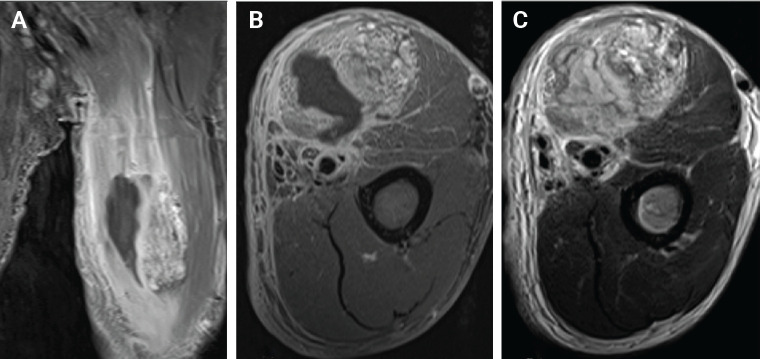

肌肉内血管瘤在肌肉骨骼疼痛鉴别诊断中很少被考虑,特别是在上肢,而且它们与肱二头肌内的感染性脓肿共存是非常罕见的。我们报告一个56岁男性二头肌肌内血管瘤伴脓肿形成的病例,其表现为左上臂疼痛和肿胀,热感,发红,肘关节屈曲和前臂旋后受限。c反应蛋白水平高(25.43 mg/dL),术前左上臂和肘部运动,视觉模拟评分为10分。x线平片示3个小静脉。磁共振成像显示二头肌左侧有一个界限不清的强化病灶(2.5×2.7×9.8 cm),病灶内t1加权信号增强,病灶内有一个小、圆、低信号强度的病灶,与肌内血管瘤一致,二头肌内侧有一个地理上的非强化区域,与感染性肌炎合并脓肿形成一致。我们进行了手术切除肌肉内血管瘤和引流脓肿在二头肌。术后5周,所有功能限制均消除,5个月随访无复发。

Intramuscular hemangiomas are rare in musculoskeletal pain differentials, especially in the upper extremities. We report a case of a 56-year-old male with an intramuscular hemangioma and abscess in the biceps brachii, presenting with pain, swelling, and limited elbow movement. High C-reactive protein (25.43 mg/dL) and visual analog scale score of 10 were noted. Radiograph showed 3 phleboliths. MRI revealed an enhancing lesion (2.5×2.7×9.8 cm) and abscess. We performed surgery for excision of the intramuscular hemangioma and drainage of the abscess in the biceps muscle. By 5 weeks post-surgery, all functional limitations had resolved, and no recurrence was observed at the 5-month follow-up.